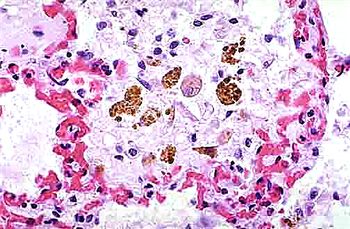

巨噬細(xì)胞系是一個(gè)總稱,包括了網(wǎng)狀內(nèi)皮系統(tǒng)(Reticuloendothelial System, RES)在內(nèi)的所有具吞噬作用的細(xì)胞。這些細(xì)胞廣泛分布于機(jī)體的各種組織和器官中,包括但不限于肺部、肝臟、腦、骨骼等。根據(jù)不同的組織定位和功能,巨噬細(xì)胞被進(jìn)一步細(xì)分為多種類型,如肺泡巨噬細(xì)胞、肝臟Kupffer細(xì)胞、小膠質(zhì)細(xì)胞、破骨細(xì)胞等。這些細(xì)胞在形態(tài)、表型和功能上均有所差異,但共同點(diǎn)是都具有強(qiáng)大的吞噬能力。

圖1